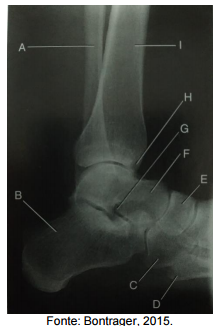

Analise a figura a seguir, que apresenta uma imagem de uma radiografia em perfil do

tornozelo.

Assinale a alternativa que apresenta a correta correlação entre a indicação e a estrutura na imagem tomográfica.